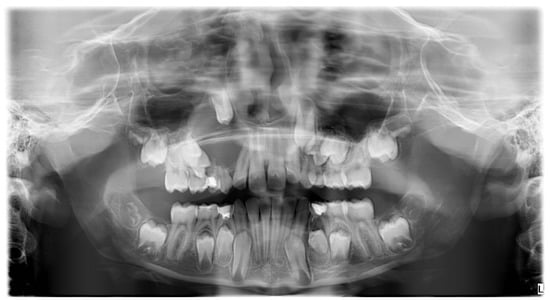

A preliminary investigation with a panoramic radiogram was ordered to disclose the presence of erupted and unerupted teeth with their possible developmental or positional abnormalities, as well as to assess the condition of surrounding maxillofacial structures. The radiolucent, unilocular area with a diameter of approximately 3 cm, extending in the area above Teeth 53 and 54, was observed (Figure 3).

Figure 3.

OPG before treatment.

That finding necessitated further diagnostics with CBCT (Figure 4, Figure 5, Figure 6 and Figure 7). A 3D radiograph confirmed a round, well-demarcated, noninflammatory cyst-like lesion extending from Teeth 11 to 15.